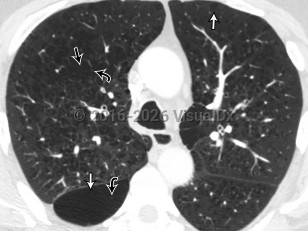

Chest pain, Dyspnea, 50-59 year old Female